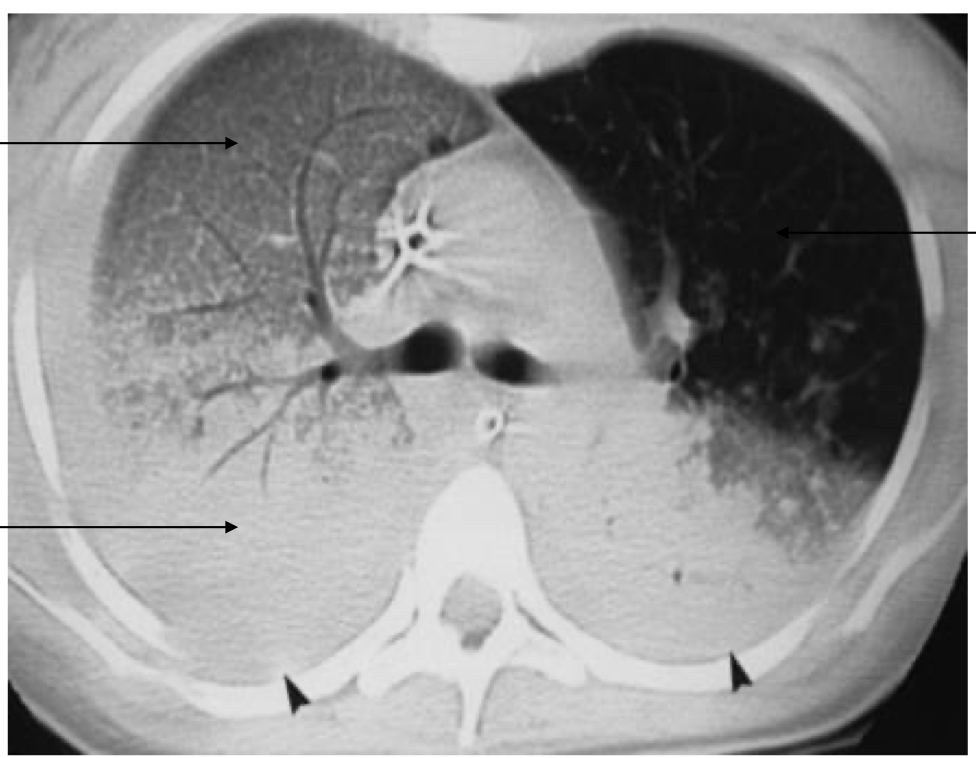

characteristic CT findings in ARDS

ground glass opacities